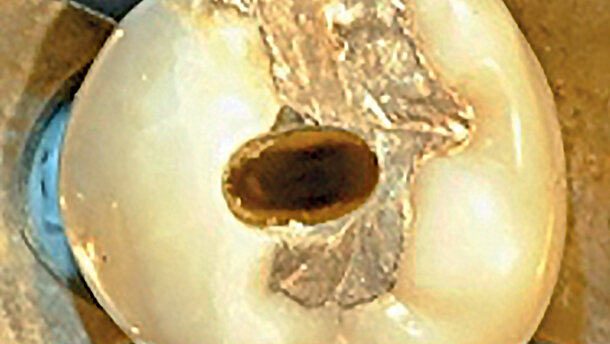

Obr. 7: Dolní molár s téměř úplnou kalcifikací dřeňové dutiny před ošetřením kořenových kanálků, provedeným skrz dva dokonale vymezené přístupové vstupní otvory, zanechávající 0,75 mm vysokou úžinu mezi dřeňovou dutinou. Všimněte si konečných výsledků ošetření v apikální třetině každého kanálku. (Fotografie: Dr. N. Pushpak)